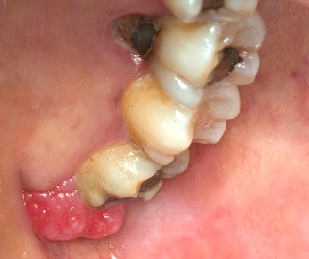

What is the clinical finding?

Pyogenic Granuloma

We can see the corresponding radiograph;

-although the radiograph suggests generalized bone loss, there is a lot of calculus on

the distal of #16 > it makes sense that this is a pyogenic granuloma